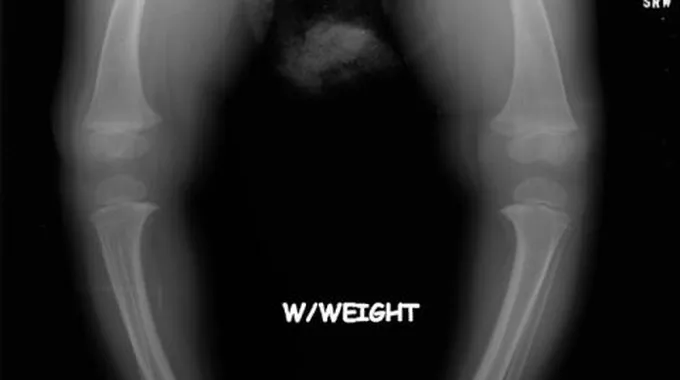

- انحناء الساقين لدى الأطفال صغار السنّ الذين بدؤوا بالمشي.

يُمكن للطبيب تشخيص مرض الكساح من خلال إجراء الفحص الجسدي للطفل، ويُمكن من خلال الضغط على العظام برفق الكشف عن مدى وجود ألم العظام أو ألم العظام عند اللمس، وهُناك العديد من الفحوصات التي من شأنها المُساعدة على تشخيص مرض الكساح، نذكر منها ما يلي:[١]

- فحص العظام بالأشعة السينية للكشف عن وجود تشوّهات في العظام.